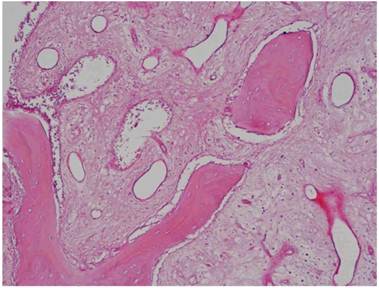

The histological results proved that the samples collected from the “test-side” after 106 days with the adding of PRF “were constituted by lamellar bone tissue with acellular osteocyte lacunae and an intensely-eosinophilic bone matrix mixed with fragments of lamellar bone tissue with inhabited osteocyte lacunae and a slightly-eosinophilic bone matrix (probably to be ascribed to the newly-formed bone tissue). In such fragments, osteocytes are sometimes disposed horizontally and border the bone trabeculae. The interposed stroma is relaxed and richly vascularized” (Figure 1/a - b - c).

Instead, the samples collected from the “Control-Side” revealed that “the fragments were constituted by trabeculae of lamellar bone tissue with inhabited osteocyte lacunae, immersed in a dense poorly-cellular fibrous stroma, in which are included fragments of lamellar bone with empty osteocyte lacunae and with an intensely-eosinophilic bone matrix. We also find roughly globular lacunae, optically empty, probably as a result of the granules of Bio-Oss not yet integrated into the bone matrix”. (Fig. 1/d)

Fig 1

a-b-c: Histological pictures referring to Test-Side of “EARLY Protocol”. d: Histological picture referring to Control-Side of “EARLY Protocol”.